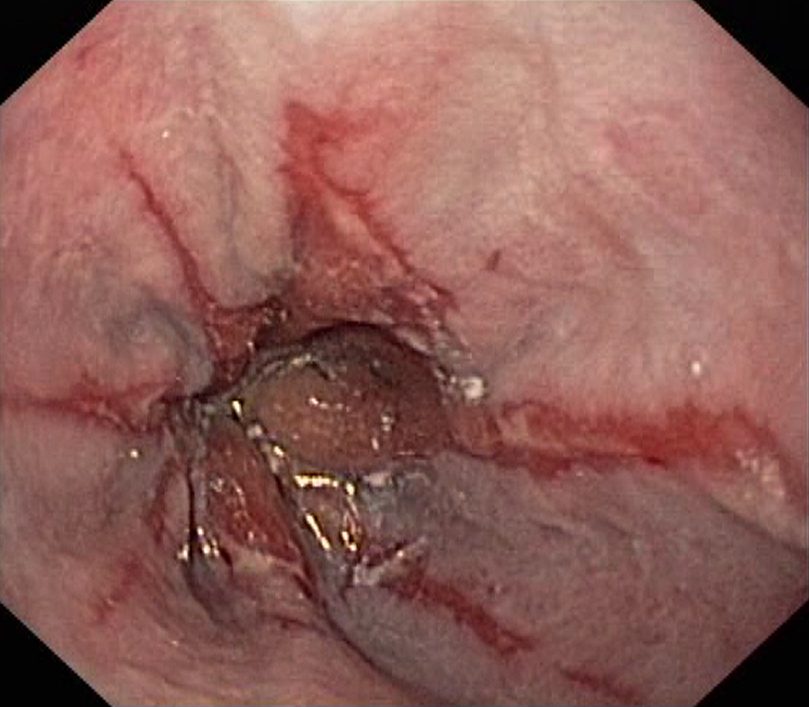

Reflux Oesophagitis Grade D (LA Classification). Just click on a picture!

Reflux Oesophagitis Grade D (LA Classification)